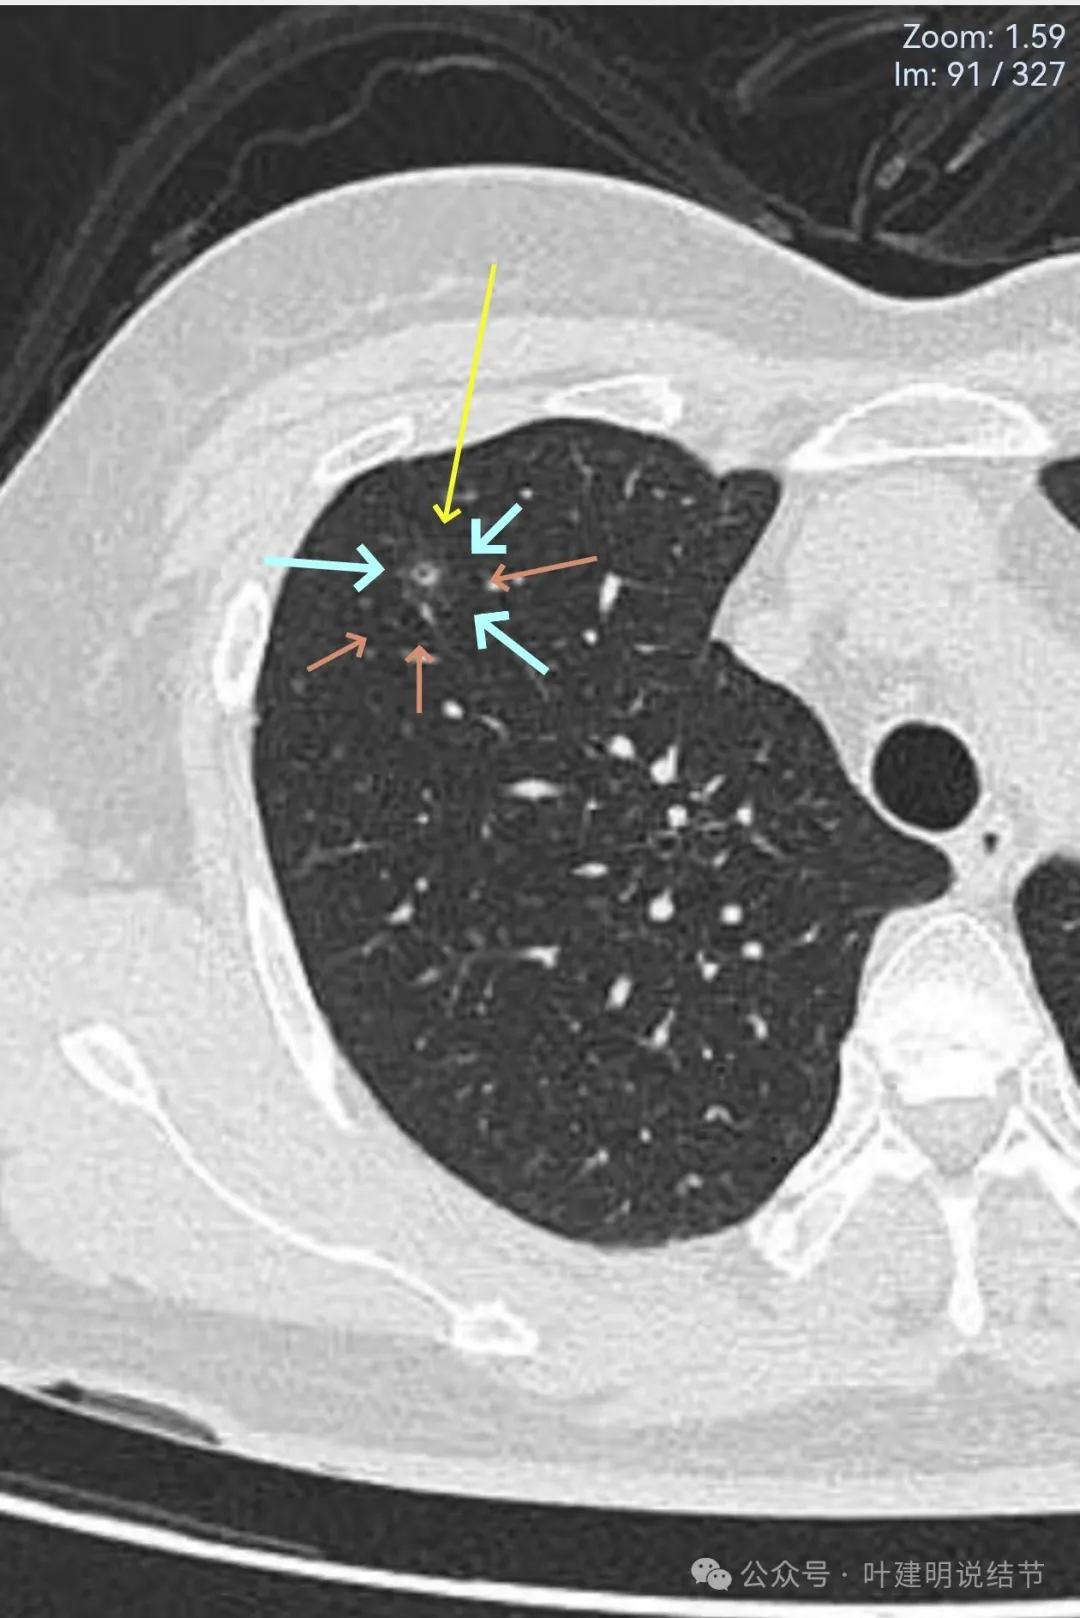

有血管经过病灶处,但距离这么近,血管却没有被影响或形成血管弯。绿色箭头处距病灶有一定距离,但也有淡而模糊的磨玻璃影。

病灶附近多发微小空泡样结构(砖色箭头),病灶边缘轮廓不清(如天蓝色箭头所示),病灶内部有实性密度伴空泡征的结节。

绿色箭头所示的磨玻璃影与主病灶并不相连的;主病灶轮廓不清;附近许多小空泡样结构;血管没有异常增粗或进入病灶内。

2023年8月时主病灶的样子,与2024年的几乎没有变化。